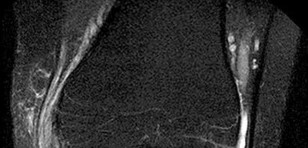

Question 3:

A 15-year-old male presents with worsening knee pain. Radiographs reveal a metaphyseal aggressive bone lesion with a 'sunburst' periosteal reaction and Codman's triangle. Biopsy confirms a high-grade intramedullary osteosarcoma. What is the standard algorithmic approach to treatment for this patient?

Correct Answer: Neoadjuvant chemotherapy followed by wide surgical resection and adjuvant chemotherapy

The standard of care for high-grade classic intramedullary osteosarcoma is neoadjuvant (pre-operative) chemotherapy, followed by wide surgical resection (either limb salvage or amputation), and then adjuvant (post-operative) chemotherapy. The percentage of histologic necrosis seen in the resected specimen after neoadjuvant chemotherapy is one of the strongest prognostic indicators for long-term survival.